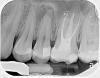

sus Опубликовано 23 апреля, 2013 Автор Поделиться Опубликовано 23 апреля, 2013 (изменено) Вот сейчас задумалась над комментарием Михалыч007 по поводу гранулемы (?) у корня 25го - кость может сама восстановиться, если сделан только канал, без резекции, несмотря на то, что в ней имеет место воспаление в замкнутом пространстве? Зуб на кальции не вели, просто сразу сделали канал. Добыла снимки этого года, до и после канала в 25, и результат по 26 с прошлого года виден (как и предсказывал Михалыч007, там оказалось еще 2 ненайденных канала). И еще мне по новому снимку кажется, что гранулема "охватывает" еще и корень 24-го, я права? Буду благодарна за комментарии по поводу проведенного лечения и прогнозы! Изменено 23 апреля, 2013 пользователем sus Ссылка на комментарий

DmitrySH Опубликовано 24 апреля, 2013 Поделиться Опубликовано 24 апреля, 2013 Вот сейчас задумалась над комментарием Михалыч007 по поводу гранулемы (?) у корня 25го - кость может сама восстановиться, если сделан только канал, без резекции, несмотря на то, что в ней имеет место воспаление в замкнутом пространстве? Зуб на кальции не вели, просто сразу сделали канал. Добыла снимки этого года, до и после канала в 25, и результат по 26 с прошлого года виден (как и предсказывал Михалыч007, там оказалось еще 2 ненайденных канала). И еще мне по новому снимку кажется, что гранулема "охватывает" еще и корень 24-го, я права? Буду благодарна за комментарии по поводу проведенного лечения и прогнозы! Да, кость может восстановиться и без применения паст с кальцием. В вашем случае убрали источник инфекции - погибший нерв. Если все было хорошо обработано и продезинфицировано, то прогноз благоприятный. Но, на всех зубах кариес и дефекты пломб на контактных поверхностях. Обязательно нужно этим заняться иначе микроорганизмы доберутся до каналов и прогноз будет плохой. Ссылка на комментарий